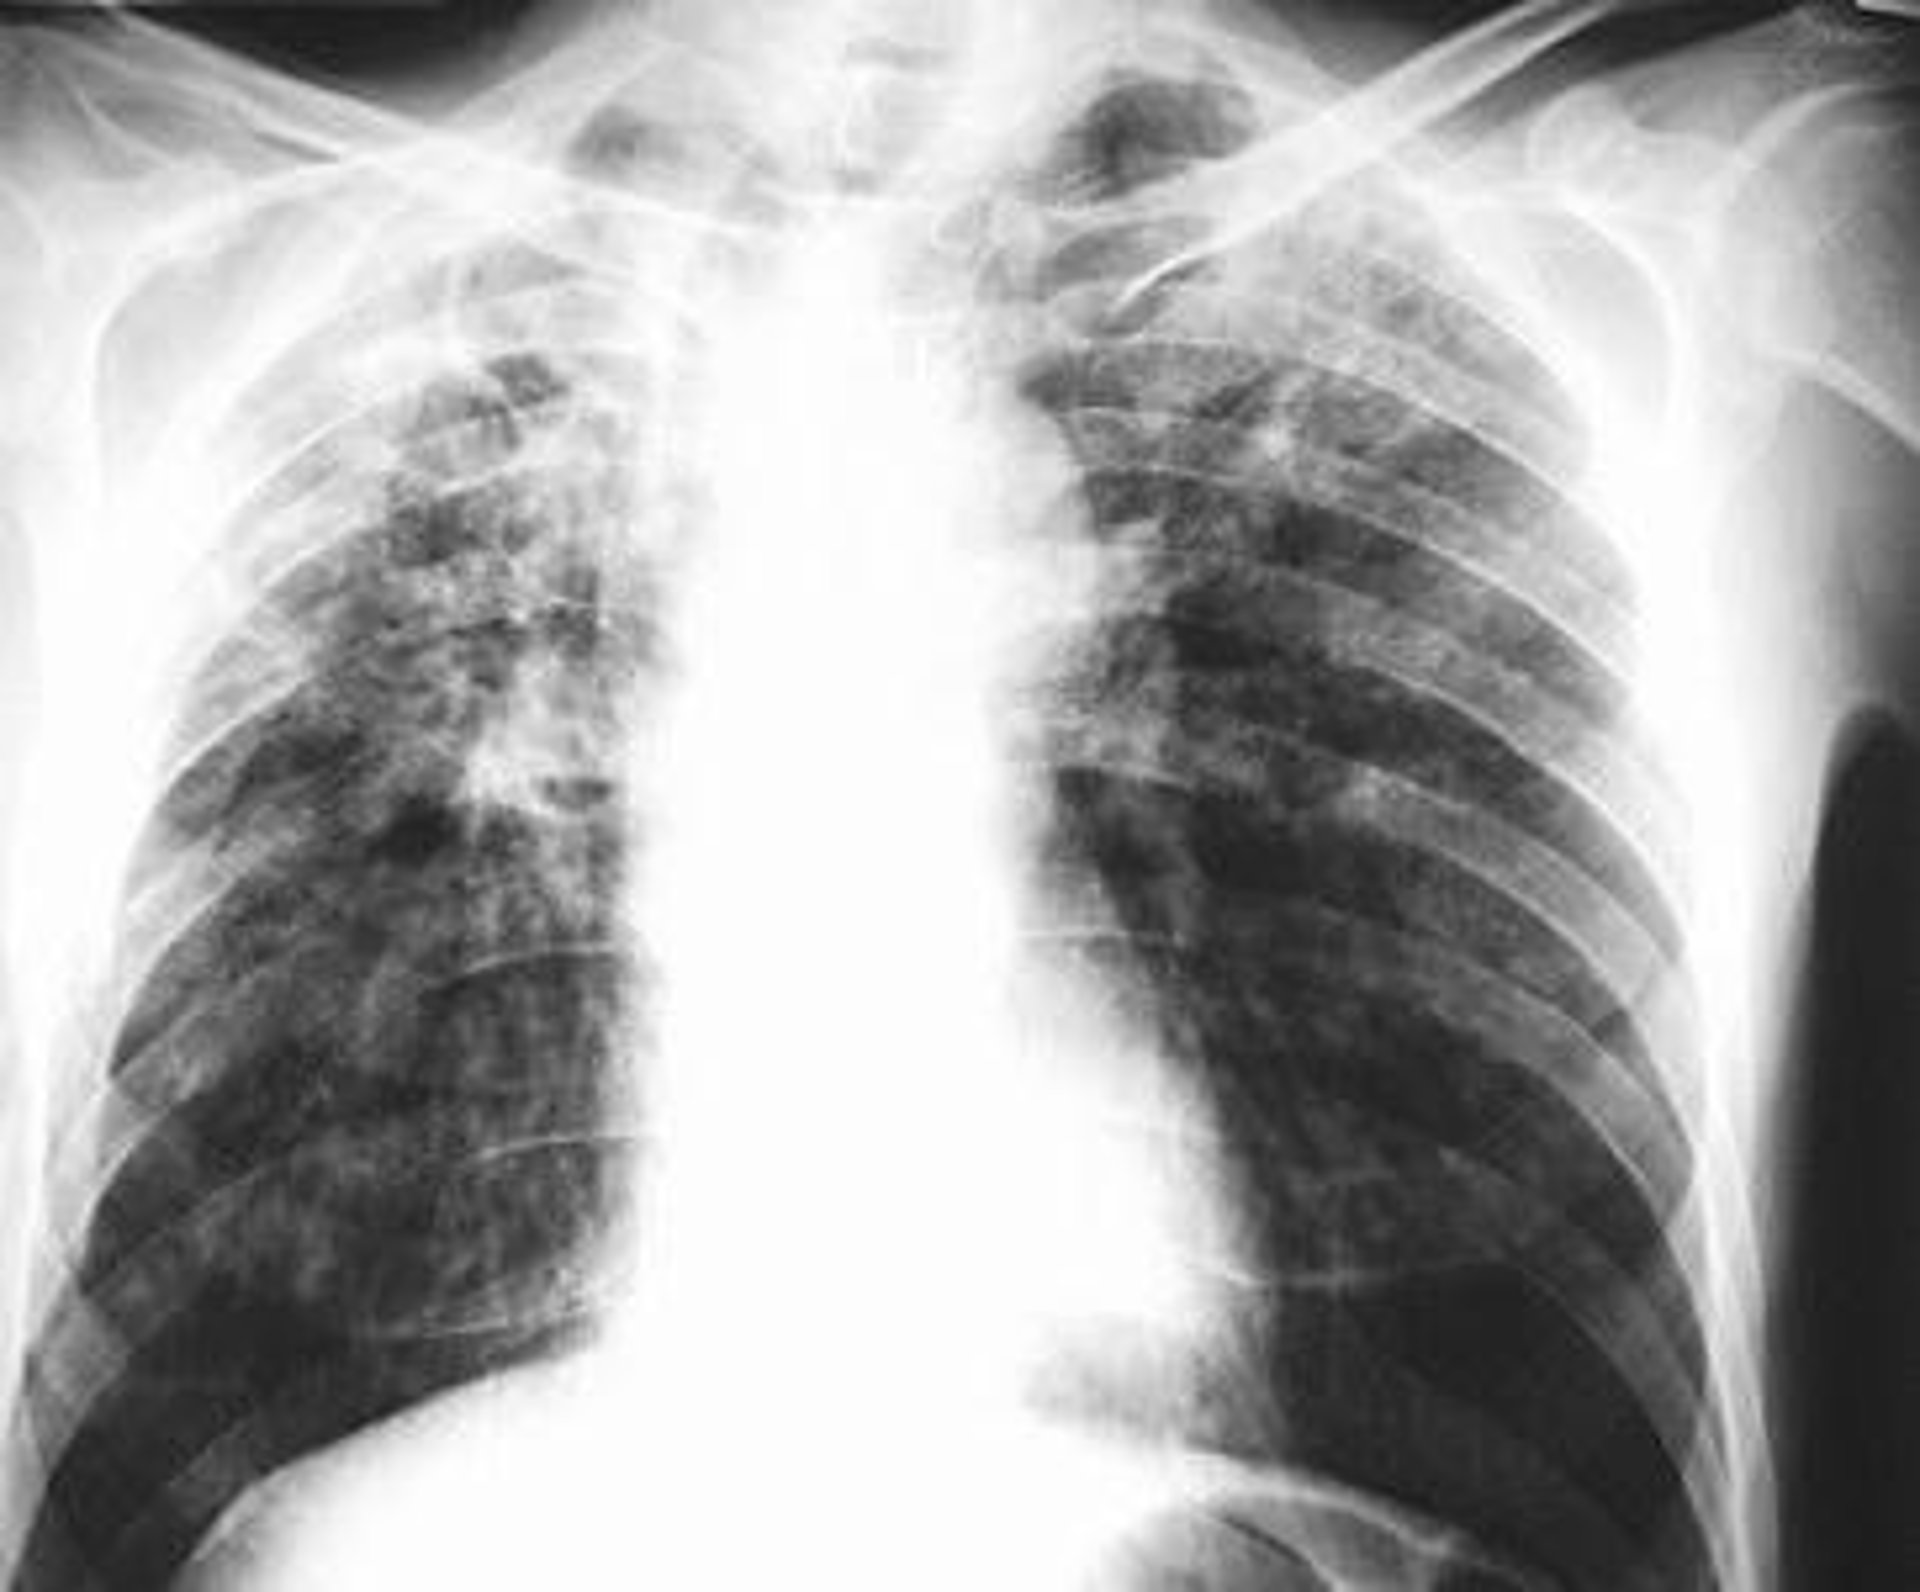

Pulmones

KRZYSZTOFM